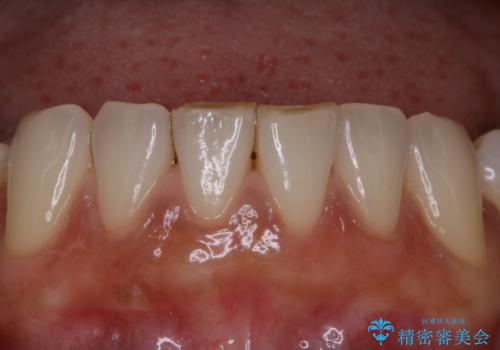

全体の総合的な治療前にPMTC

- 歯科がだいぶ久しぶりで、全額的な治療の前にクリーニングを希望されました。PMTC60分コースを行いました。

歯にステイン(着色)や歯石などが付着していると、汚れなのか虫歯なのかの判別が分かりにくく、正確な診断ができないことがあります。

そのため、治療前には専門的な機械や材料を使用したクリーニング(PMTC)をすることで、ご自身本来の歯の状態となります。より、精密な治療前を行うためには、治療前などにPMTCを行いお口の中の環境を綺麗にすることがおすすめです。